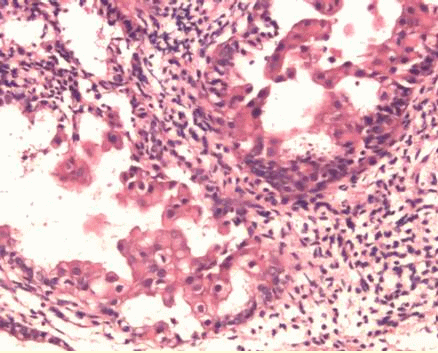

(单选题)镜下局部腺体如图所示,诊断考虑为()

A:子宫内膜不规则增生

B:局部复杂性增生

C:嗜酸性乳头状化生

D:嗜酸性不典型乳头状化生

E:子宫内膜上皮内瘤变

第3题,共3个问题

(单选题)鉴别的主要依据是()

A:月经经期延长

B:腺体结构复杂

C:嗜酸性芽胞状细胞乳头,无非典型性

D:嗜酸性芽胞状细胞乳头,有非典型性

E:与周围组织形成明显反差,伴有细胞非典型性